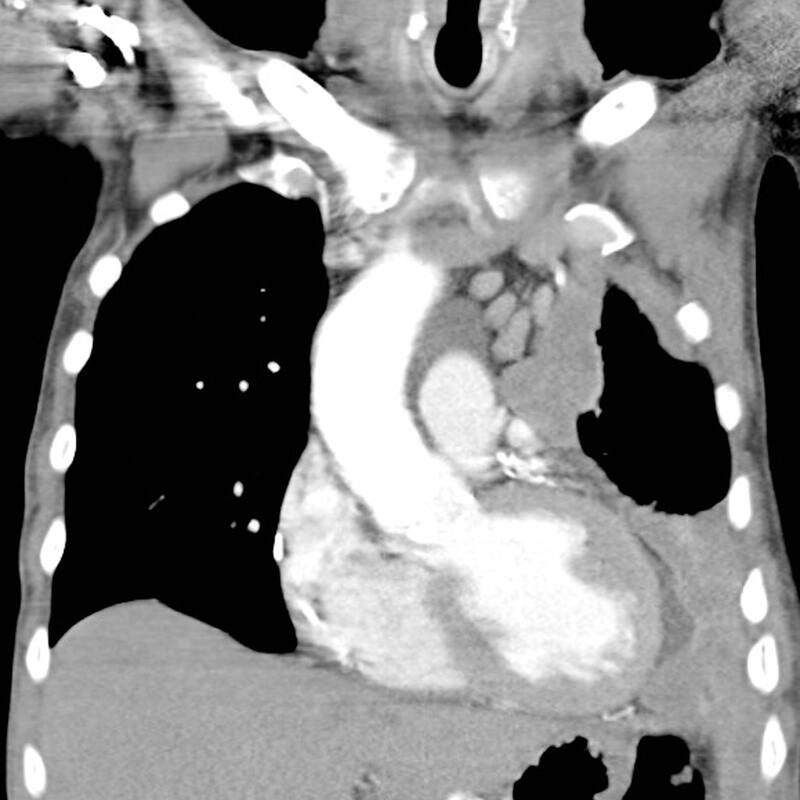

Frente a esta realidad, la destacada revista científica internacional Natura Genetics, publicó un artículo sobre el estudio molecular del tumor mesotelioma pleural maligno (MPM), ocasionado por la exposición al asbesto, titulado “Multiomic analysis of malignant pleural mesothelioma identifies molecular axes and specialized tumor profiles driving intertumor heterogeneity”, sobre la investigación desarrollada en Francia por el académico del Instituto de Ciencias de la Ingeniería (ICI) de la Universidad de O’Higgins (UOH), Dr. Alex Di Genova, mientras realizaba su segundo postdoctorado en el equipo de genomas de cáncer raros en la International Agency for Research on Cancer (IARC).

Sumado a lo anterior, el académico de la UOH enfatiza que otro de los grandes beneficios de secuenciar el genoma completo para su análisis, fue lograr describir por primera vez procesos mutacionales cuya existencia era desconocida en este tipo de tumor. “Por ejemplo, en un 25% de los tumores detectamos un proceso que se llama ‘cromotripsis’, que es una crisis a nivel de uno o dos cromosomas, donde ese cromosoma se reorganiza, generando una ventaja y permitiendo un desarrollo celular más acelerado. Eso es un proceso de evolución puntual que no se había descrito antes”, puntualiza el científico.